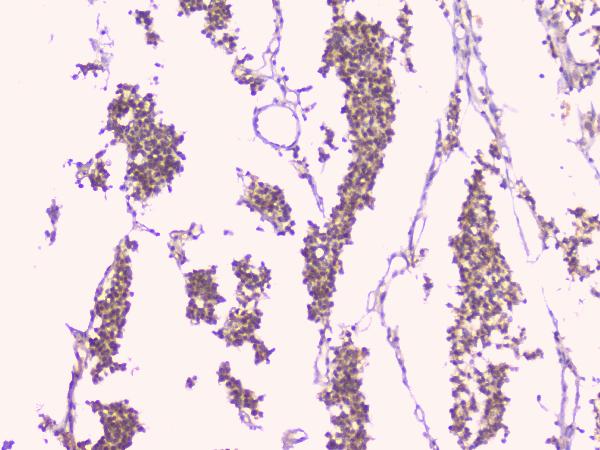

IHC analysis of OPG/TNFRSF11B using anti-OPG/TNFRSF11B antibody (A00863).

OPG/TNFRSF11B was detected in a paraffin-embedded section of human lung cancer tissue. Biotinylated goat anti-rabbit IgG was used as secondary antibody. The tissue section was incubated with rabbit anti-OPG/TNFRSF11B Antibody (A00863) at a dilution of 1:200 and developed using Strepavidin-Biotin-Complex (SABC) (Catalog # SA1022) with DAB (Catalog # AR1027) as the chromogen.